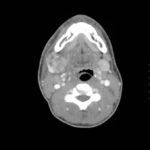

The computed tomography (CT) scan demonstrates prominent enlargement and heterogeneous enhancement of the right submandibular gland (single large arrow) compatible with sialadenitis. There is no evidence of a sialolith or obstruction on the CT. There is associated edema (two small arrows) of the right submandibular space, parapharyngeal space and anterior right neck with partial effacement of the right vallecula and right pyriform sinus.